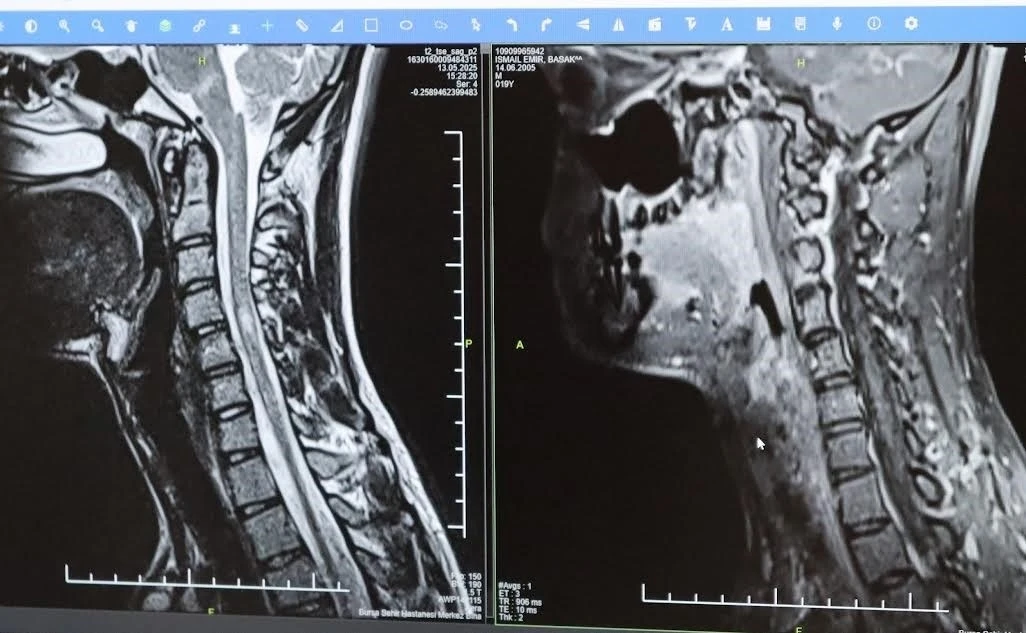

Bursa Şehir Hastanesinde görevli Nöroloji Uzmanı Prof. Dr. Özden Kamışlı, 30 Mayıs Dünya MS Günü kapsamında açıklamalarda bulundu. MS’in, bağışıklık sisteminin sinir sistemine saldırmasıyla gelişen kronik bir hastalık olduğunun bilgisini veren Prof. Dr. Kamışlı, "Dünyada yaklaşık 2.8 milyon MS hastası olduğu bilinmektedir. MS genellikle 20-40 yaş arası gençleri etkilemektedir. Bununla birlikte çocukluk döneminde ya da ileri yaşta da ortaya çıkabilmektedir. Kadınlarda görünme sıklığı erkeklere göre bir buçuk kat daha fazladır" dedi.

MS hastalarının çeşitli şikâyetlerle hekimlere başvurduğunu vurgulayan Kamışlı, "Bunlar arasında görme bozukluğu, kol ve bacakta kuvvetsizlik, uyuşmalar, dengesizlik, yürüme bozukluğu, idrar problemleri veya aşırı yorgunluk ve halsizlik hali bulunmaktadır. MS ataklarla seyredebilir ve genellikle en sık görülen formu budur. Birdenbire bir şikâyet ortaya çıkar ve zamanla azalır veya kaybolur. Bir de progresif dediğimiz ilerleyici formu vardır. Bu ilerleyici formda hastalık yavaş yavaş ilerlemektedir. MS her hastada farklı seyreder. Bu nedenle tek tip bir MS hastalığından bahsetmek mümkün değil" şeklinde konuştu.

Hastalığın tanısını ne kadar erken konulursa ve tedaviye ne erken başlanırsa; hastaların günlük hayatta aktif ve üretken bir şekilde devam etmelerinin o kadar kolaylaştığına dikkat çeken Kamışlı, "Günümüzde MS’le ilgili çok fazla gelişme oldu ve tedavi seçenekleri arttı. MS merkezlerinde bu tedavi seçeneklerine ulaşmaları mümkün. Hastalarımız için doğru tanı, düzenli takip ve uygun tedavi oldukça önem teşkil etmektedir" diye konuştu.